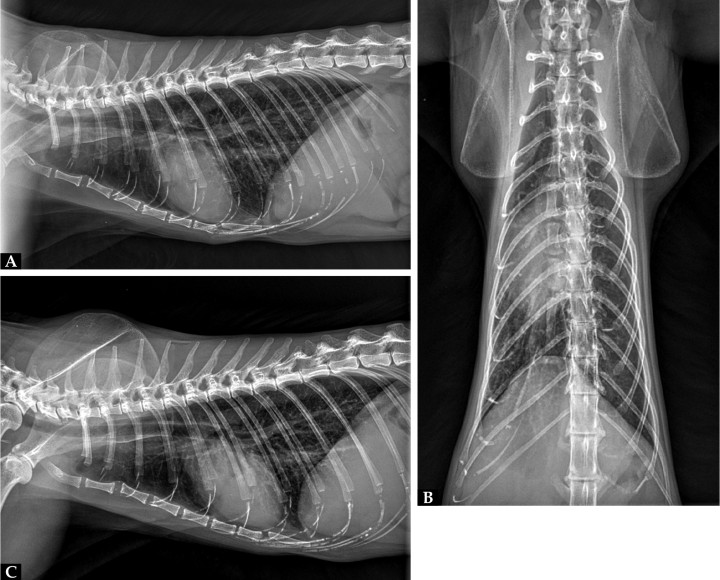

La ecografía abdominal no reveló alteraciones significativas, y los órganos y estructuras evaluados se encontraron dentro de la normalidad. Las radiografías torácicas en tres proyecciones no mostraron signos radiológicos significativos, mostrando una imagen del patrón pulmonar, mediastino y silueta cardiaca normales y sin evidencias claras de masas o efusión pericárdica (Fig. 2).

Imágenes radiográficas. (A) Proyección lateral derecha. (B) Proyección ventrodorsal. (C) Proyección lateral izquierda.